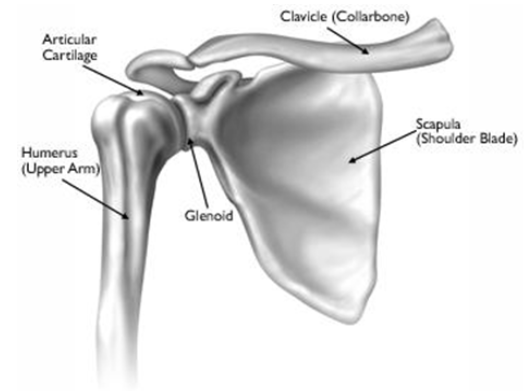

Normal Anatomy: Shoulder

A